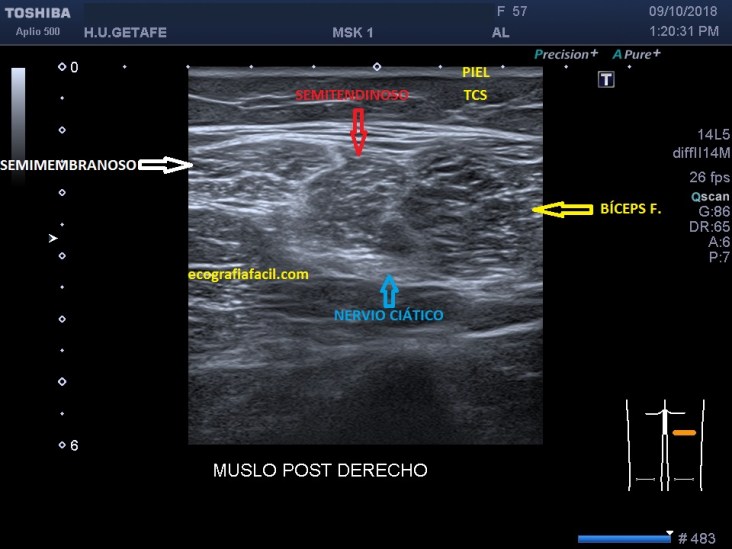

Los isquiotibiales son muy estudiables con ecografía en el tercio medio del fémur, ahí son muy superficiales y van los tres músculos unidos, justo superfial al Nervio Ciático que va más profundo que estos. Si consultas el Netter y miras la siguiente foto que te pongo, verás que la correlación anatomo-ecográfica en el tercio medio es perfecta en este corte axial o transverso.

Estos músculos son hipoecogénicos, separados por una línea de separación hiperecogénica.

Estos músculos pueden seguirse ecográficamente desde proximal a distal y de interno en la parte proximal, a externo el Bíceps Femoral e interno, el Semimembranoso y el Semitendinoso, que antes de buscar su inserción y en el tercio distal del fémur, se posicionan uno sobre otro…así…Este corte es muy distal y transverso: